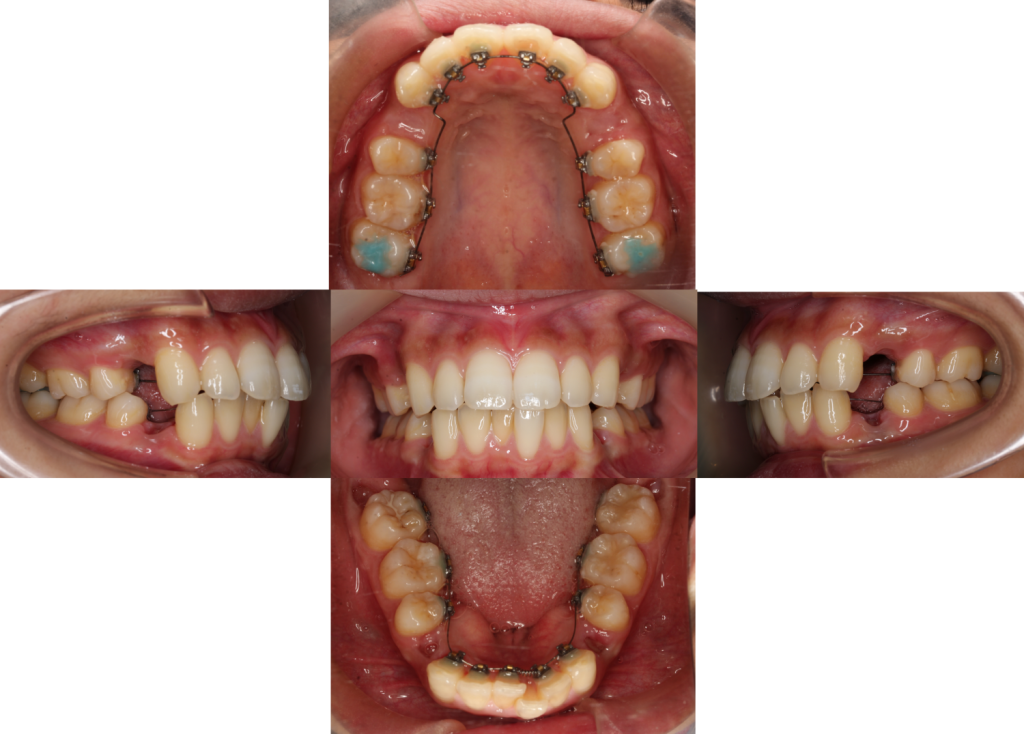

上下抜歯をし、装置を装着しました。まずは歯のガタツキを整えます。

装置を噛んでしまわないように、上の奥歯にバイトアップという青いレジンをつけています。